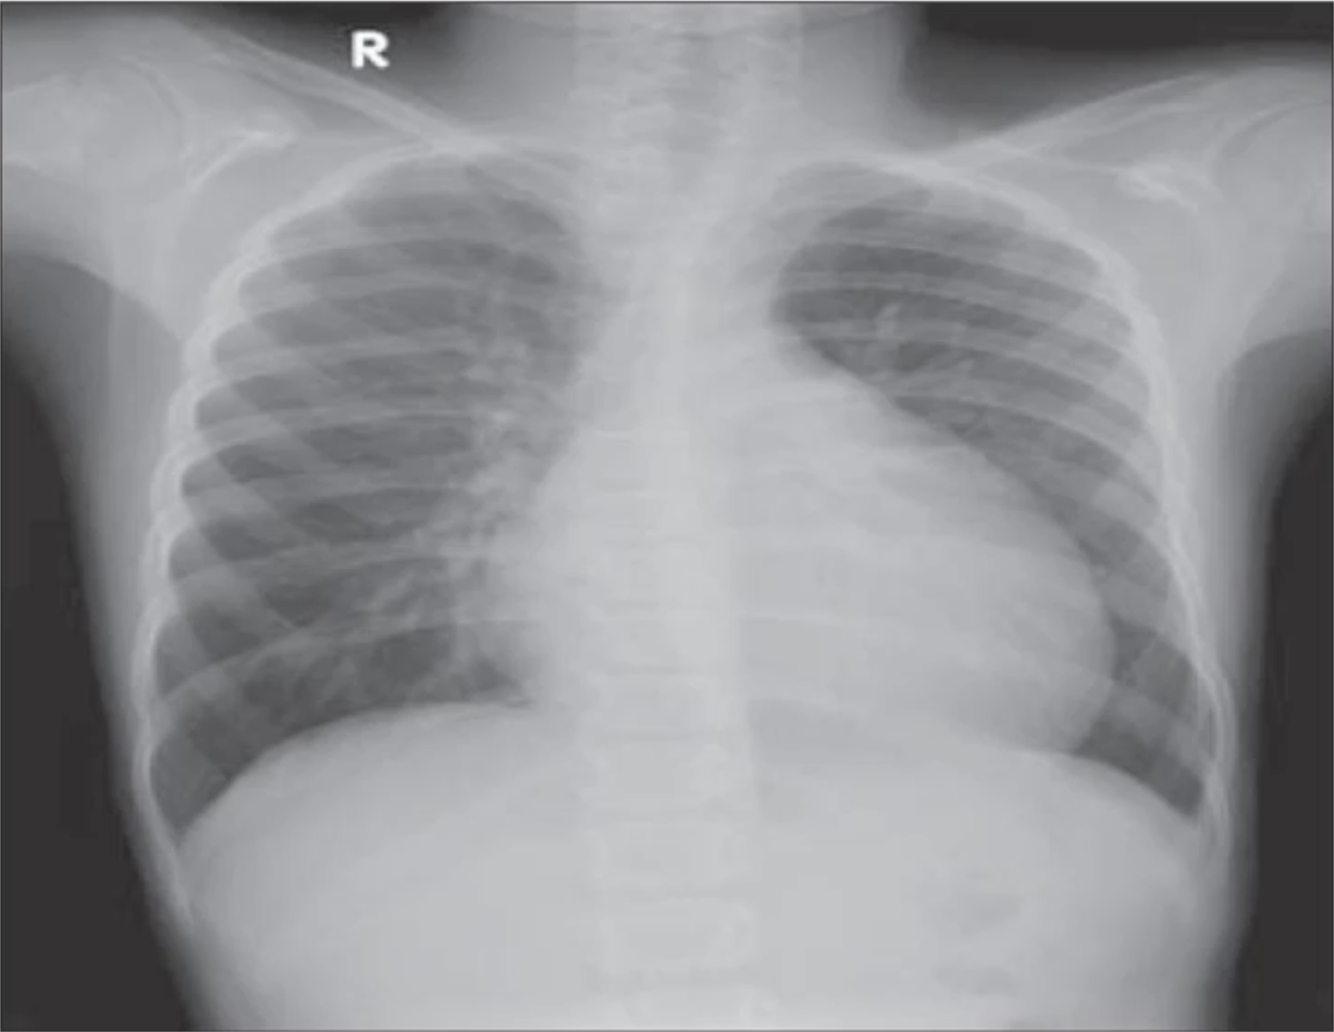

A Pneumothorax patient improved after chest drain insertion. However, they complain of recurrent SOB after 2 hours. What is the cause of the recurrent SOB indicated by the repeat CXR seen here?

Re-expansion Pulmonary Oedema as a complication of Chest Drain insertion.